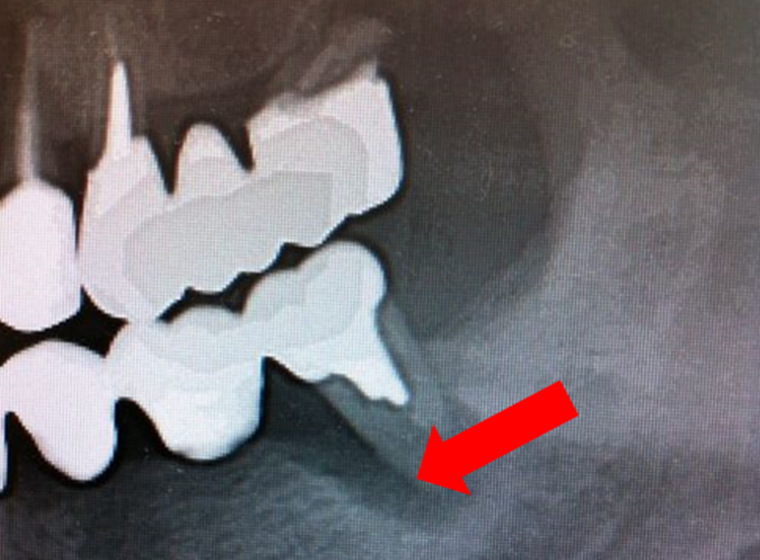

-

左の画像の黒い部分が顎の骨が溶かされている、部分的な歯周病である「斜状吸収」の状態です。治療後3年すると白く写り、顎の骨が増加しているのが分かります。

-